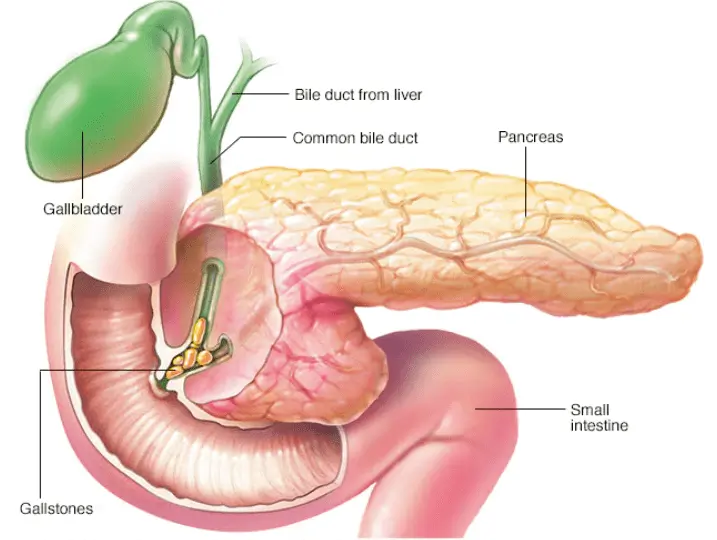

Анатомия и особенности Гартманова кармана желчного пузыря